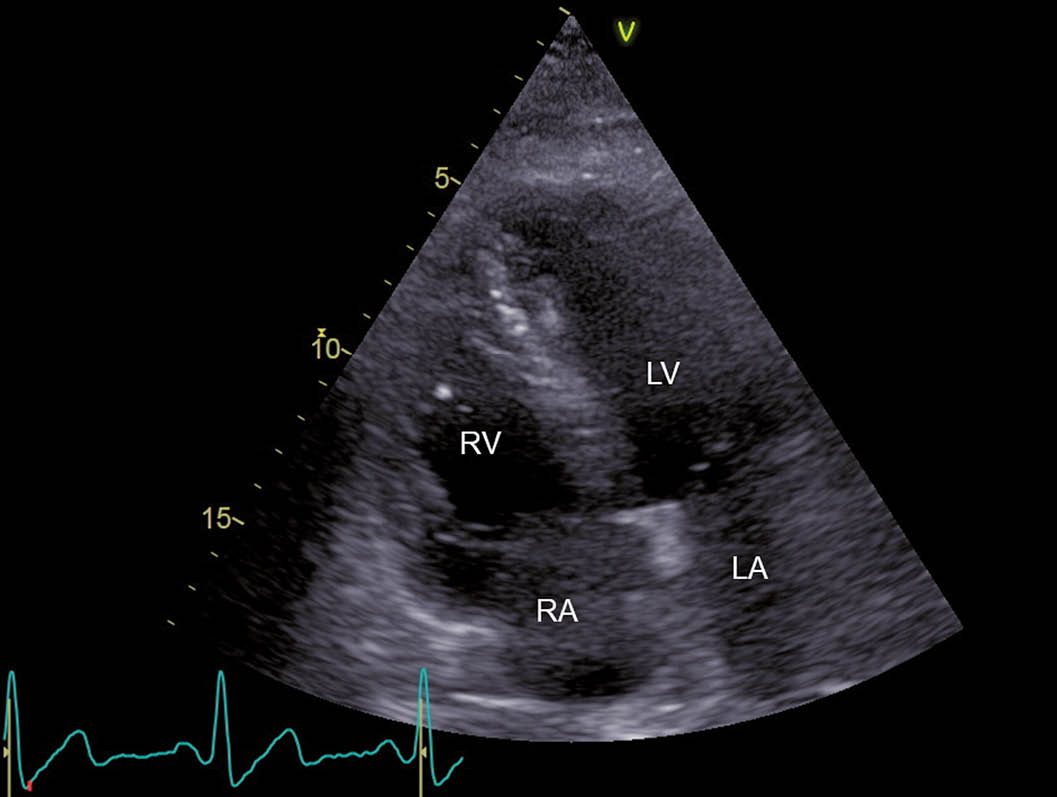

Abb. 2: CW-Doppler-Signal des Flusses durch die Trikuspidalklappe

Es zeigt sich ein schneller systolischer Regurgitationsjet. Der daraus errechnete systolische Druckgradient zwischen rechtem Ventrikel und rechtem Atrium liegt bei 89mmHg, was für eine schwere pulmonalarterielle Hypertonie spricht.